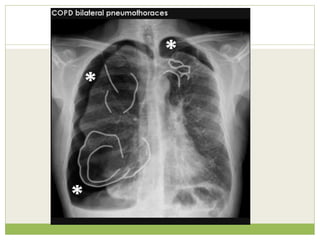

PNEUMOTHORAX

๏‚— A Primary Pneumothorax is one that occurs without

๏‚— Secondary Pneumothorax occurs in the presence of

๏‚— In a minority of cases, the amount of air in the chest

๏‚— This condition is a medical emergency that can cause

CAUSES OF HYPERTRANSRADIANT ๏‚—Mastectomy โ€” absent breast ยฑ absent pectoral muscle shadows. ๏‚— Poland's syndrome โ€” unilateral congenital absence of pectoral ๏‚— muscles ยฑ rib defects. ๏‚— PLEURA PNEUMOTHORAX ๏‚— LUNG ๏‚ก EMPHYSEMA ๏‚ก UNILATERAL BULLAE โ€” vessels are absent rather than attenuated. May mimic pneumothorax. ๏‚ก MACLEOD'S SYNDROME โ€” the late sequela of childhood bronchiolitis. Small lung with small main and peripheral arteries. Air trapping occurs on expiration

PNEUMOTHORAX ๏‚— A pneumothorax isan abnormal collection of air or gas in the pleural space that separates the lung from the chest wall and which may interfere with normal breathing

๏‚— A PrimaryPneumothorax is one that occurs without an apparent cause and in the absence of significant lung disease ๏‚— Secondary Pneumothorax occurs in the presence of existing lung pathology. ๏‚— In a minority of cases, the amount of air in the chest increases markedly when a one-way valve is formed by an area of damaged tissue, leading to a Tension Pneumothorax. ๏‚— This condition is a medical emergency that can cause steadily worsening oxygen shortage and low blood pressure. Unless reversed by effective treatment, these sequelae can progress and cause death.